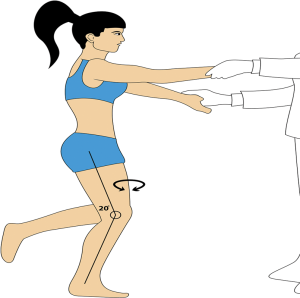

- تست تسالی (Thessaly test): تست تسالی یک روش ارزشمند و با دقت تشخیص بالا جهت معاینه فیزیکی مبتلایان به آسیب دیدگی های حاد زانو می باشد که برای تشخیص پارگی منیسک بکار میرود. طبق تحقیقات و مقایسه های انجام شده نتیجه تست تسالی نسبت به تست های مک موری و یافتن تندرنس در خط مفصلی دقیق تر می باشد. جهت انجام این تست بیمار ایستاده و کف پای خود را روی زمین قرار می دهد. در همین حالت پزشک دست های بیمار را در وضعیت صاف و کشیده می گیرد و از بیمار در خواست می کند که یکی از زانوهای خود را ۲۰ درجه خم کرده و سه مرتبه حرکت چرخشی به داخل و خارج را انجام دهد.

تصویر شماره شش : نحوه انجام تست تسالی